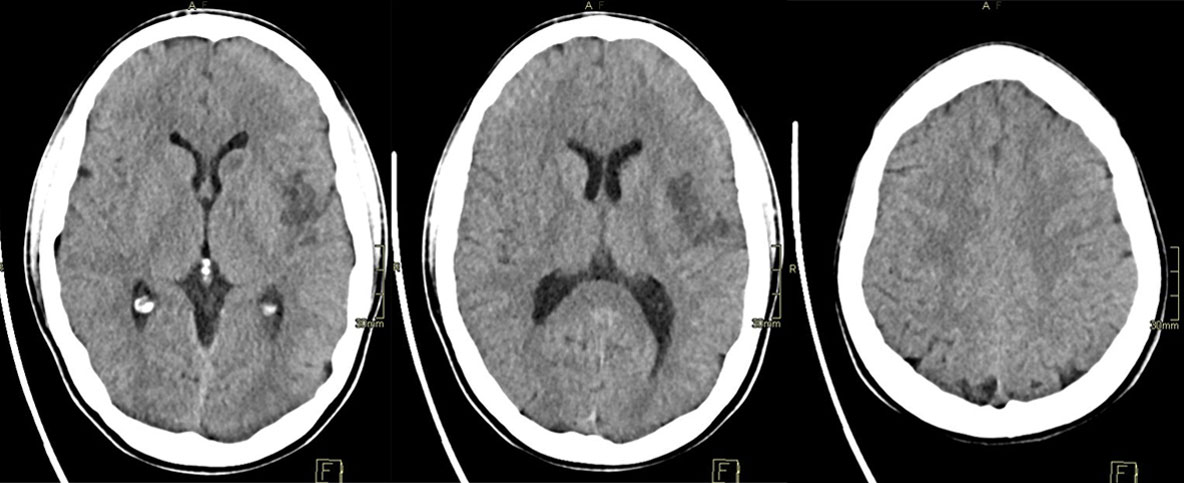

24h CT-scan

24h CTA and CTP